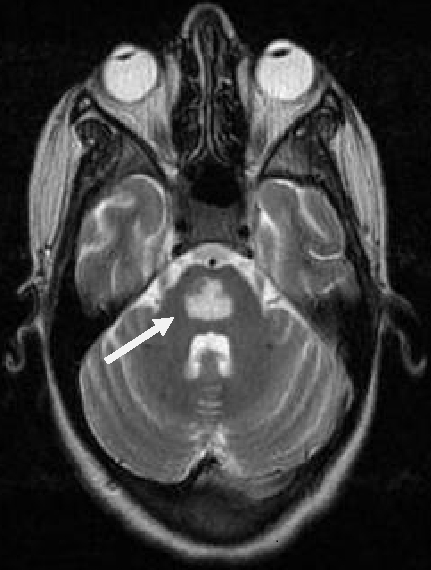

Patiente âgée de 18 ans, primipare, enceinte de 12 semaines d'aménorrhées, sans antécédents, a été admise aux urgences pour prise en charge de vomissements gravidiques incoercibles depuis trois semaines. L'examen clinique a montré un subictère, des signes de déshydrations globale, une ophtalmologie, une ataxie et une confusion. Une tension artérielle systolique à 90 mmHg, une tachycardie à 126 battements par minute. la biologie a objectivé une alcalose métabolique (ph à 7.58, HCO3- à 51.7mmol/L, Bases excès à 26.7 mmol/L, PCO2 à 56mmHg, PaO2 à 83mmHg), hyponatrémie à 130mmol /L, hypokaliémie à 1.6 mmol/L, hypochlorémie à 50mmol /L, Bilirubine directe à 40mg/L , ALAT à 1977 UI UI/L, ASAT à 543 UI UI/L, Urée à 1.6g/L, Créatinine à 14 mg/L, la sérologie des hépatites virale B et C étaient négatives, une échographie abdominale était normale. Une Encéphalopathie de Wernicke compliquant un hyperémèse gravidique a été évoquée et confirmée par IRM cérébrale. Le traitement était à base d'une réhydrations par sérum salé et glucosé et apport journalier des électrolytes, antiémétiques et vitaminothérapie à base de B1 à la dose 200mg/jour pendant un mois. L'évolution a été marquée après une semaine par l'arrêt des vomissements, retour de l'état de conscience à la normale et correction des troubles métaboliques. La patiente a quitté L'hôpital au dixième jour. Un control réalisé après 10 jours a montré des troubles de comportement. Une IRM de control a été réalisée montrant une image de myélinolyse centropentique.